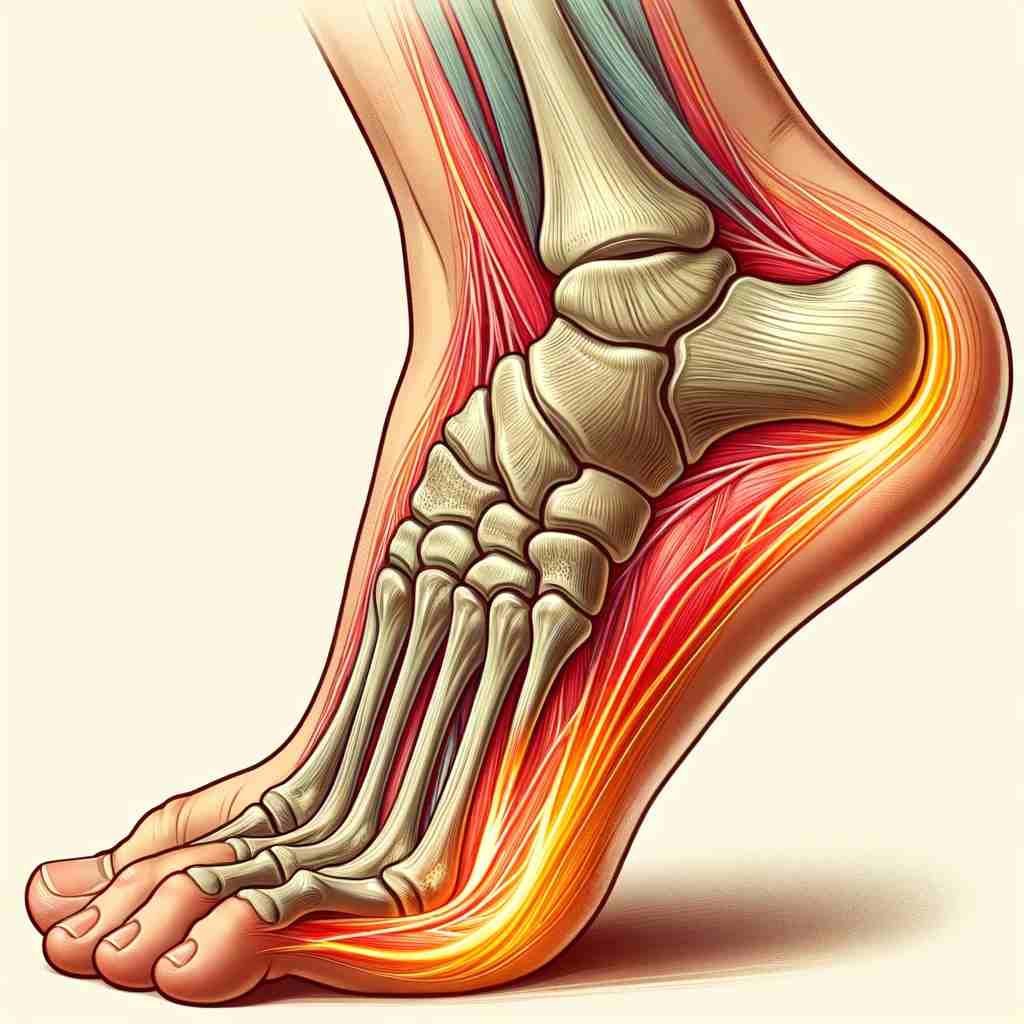

Heel Pain Causes and Treatment shop, Heel Pain Causes Diagnosis Treatment shop, 4 Heel Pain Symptoms to Take Seriously Chicagoland Foot and Ankle Board Certified Foot and Ankle Specialists and Surgeons shop, Ankle Heel Foot Pain SpinePain Solutions shop, 10 Causes of Heel Pain and When to See a Doctor Raleigh Orthopaedic shop, Heel Pain Plantar Fasciitis is a common and Painful Condition shop, Understanding Foot Pain Foot Pain Chart Foot Pain Diagram Pain Medicine Consultants Pain Specialists shop, Pain In The Back Of The Heel What Could It Mean shop, Pain In The Back Of The Heel What Could It Mean shop, Main Causes of Back of Heel Pain in North Seattle Foot and Ankle Center of Lake City shop, What Causes Heel Pain shop, Not all heel pain is Plantar Fasciitis RunningPhysio shop, Common Conditions Causing Heel Pain shop, Common Causes of Pain in the Back of the Ankles Pain Management NYC shop, Plantar Fasciitis Foot and Ankle Specialists shop, Diagnosis of Heel Pain AAFP shop, Heel pain s latest treatment techniques A Step Ahead Foot and Ankle Care shop, Ankle Heel Pain Treatment Specialists DPMC shop, Heel Pain Causes Treatment Prevention Podiatry Sydney shop, Medial Ankle Pain Tarsal Tunnel Syndrome Sports Injury Physio shop, A Stabbing Heel Pain shop, Foot Pain Conditions Causes Symptoms Treatments HSS shop, Pinpoint Your Foot Ankle Pain OrthoNebraska shop, What is heel pain Sole Podiatry shop, Foot and Ankle Pain Treatment in New Jersey RWJBarnabas Health shop, Heel Pain Causes Diagnosis and Treatment Options Joint Replacement Institute shop, Severs Disease Sever s Disease Treatment Sydney shop, Plantar Fasciitis Symptoms Causes Treatment Options shop, Ankle Pain and Plantar Fasciitis Treatment Softwave Clinics shop, Side Heel Pain What You Should Know Cellaxys shop, Foot Pain Conditions Causes Symptoms Treatments HSS shop, Effective Treatment for Heel Pain Foot Foundation shop, Heel Pain Podiatrist in Old Bridge and Sayreville NJ Jason Grossman DPM shop, Foot and Ankle Pain Treatment in Schertz BioMotion PT shop, Achilles Tendinopathy Causes Symptoms Treatment The Feet People Podiatry shop.